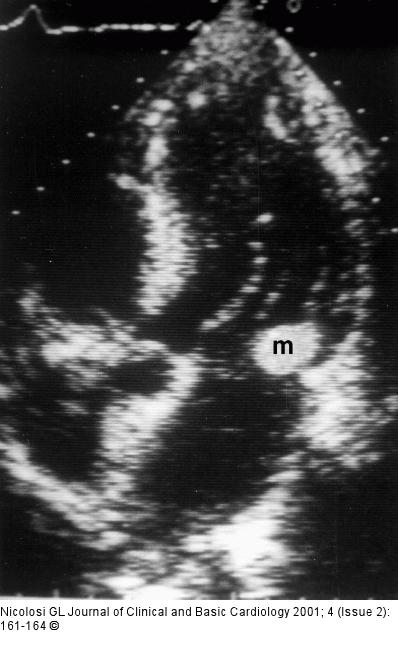

Figure/Graphic 1: Endokarditis - Diagnose - TEE Apical transthoracic 5 chamber view from a 59 year old male with fever, non-Hodgkin lymphoma and an echogenic mass, mobile in real time, at the base of the posterior leaflet of the mitral valve (m). This could be classified as a positive echocardiogram and a major Duke criteria for the diagnosis of IE (see text) |

Apical transthoracic 5 chamber view from a 59 year old male with fever, non-Hodgkin lymphoma and an echogenic mass, mobile in real time, at the base of the posterior leaflet of the mitral valve (m). This could be classified as a positive echocardiogram and a major Duke criteria for the diagnosis of IE (see text) |